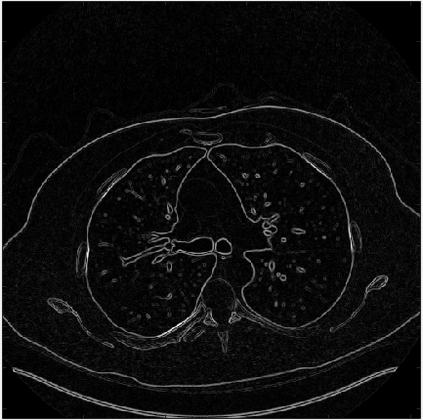

In this work, we present Eformer - Edge enhancement based transformer, a novel architecture that builds an encoder-decoder network using transformer blocks for medical image denoising. Non-overlapping window-based self-attention is used in the transformer block that reduces computational requirements. This work further incorporates learnable Sobel-Feldman operators to enhance edges in the image and propose an effective way to concatenate them in the intermediate layers of our architecture. The experimental analysis is conducted by comparing deterministic learning and residual learning for the task of medical image denoising. To defend the effectiveness of our approach, our model is evaluated on the AAPM-Mayo Clinic Low-Dose CT Grand Challenge Dataset and achieves state-of-the-art performance, $i.e.$, 43.487 PSNR, 0.0067 RMSE, and 0.9861 SSIM. We believe that our work will encourage more research in transformer-based architectures for medical image denoising using residual learning.